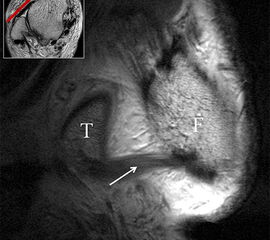

Das Ligamentum fibulotalare anterius entspricht einer bifaszikulären Struktur (Abb. 2 a) mit interponierendem fibrovaskulärem Gewebe (S. K. Sarrafian (ed). 2003). Es gibt jedoch Variationen der Ligamentanatomie. In 55% liegt das LFTA als bifaszikuläres Band (Abb. 2 a), in 9% als monofaszikuläre Bandstruktur (Abb. 2 b) und in 36% als multifaszikuläre, striäre Variante (Abb. 2 c) vor 3.

PD fs HR axial. Klare Darstellung eines filigranen, knapp über 1 mm breiten LFTA (Pfeil). Fibula (F).

Abbildung 3

Das LFTA verbindet die antero-inferiore Fibulaspitze mit dem Processus lateralis tali und inseriert hier an einem oder zwei kleinen Tuberkeln 3. Der in Neutralposition horizontale Verlauf erleichtert die kernspintomographische Darstellung in dieser Standardebene. Das LFTA weist durchschnittlich eine Breite von knapp über 2 mm auf 4. Somit sind bei einer Routinedarstellung in 3 mm Schichtdicke Anschnittsphänomene, die die Diagnostik erschweren, regelmäßig anzutreffen. Dementsprechend sind auch die ligamentären Subfaszikel nicht zu differenzieren. In koronarer Darstellung ist dies aufgrund der hohen Auflösung in der Schichtebene jedoch möglich (Abb. 2 a-c), wobei hier wiederum eine Integritätsbeurteilung des Bandes erschwert ist. Unter Verwendung hochauflösender Techniken im Millimeterbereich (Schichtdicke) sind hingegen auch in der axialen Ebene die subfaszikulären Strukturen zu beurteilen (Abb. 3).